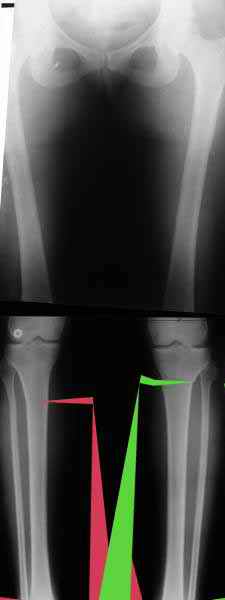

a> Из приведнной схемы не совсеим понял что означают разноцветные линии.

Черные - это нынешняя механическая ось. Красные - это планируемая правильная ось.

Из приведнной схемы не совсеим понял что означают разноцветные линии.

И зачем латерализация периферического фрагмента. Я всегда делаю медиализацию. См схему. И для данного случая медиализация подходит как нельзя лучше.